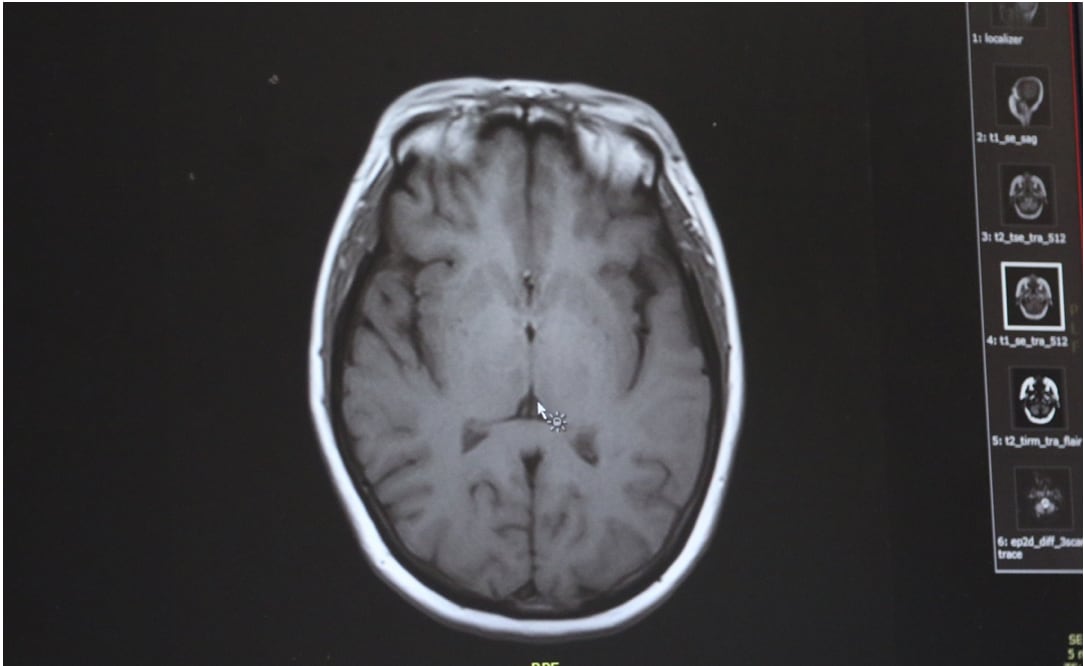

De acuerdo con los CDC, la ameba “comecerebros” suele encontrarse en agua dulce templada, como la de lagos y ríos y aguas termales, y entra al cuerpo a través de la nariz. De ahí sube al cerebro, donde destruye tejido cerebral, una condición conocida como “Primary Amebic Meningoencephalitis” (PAM).